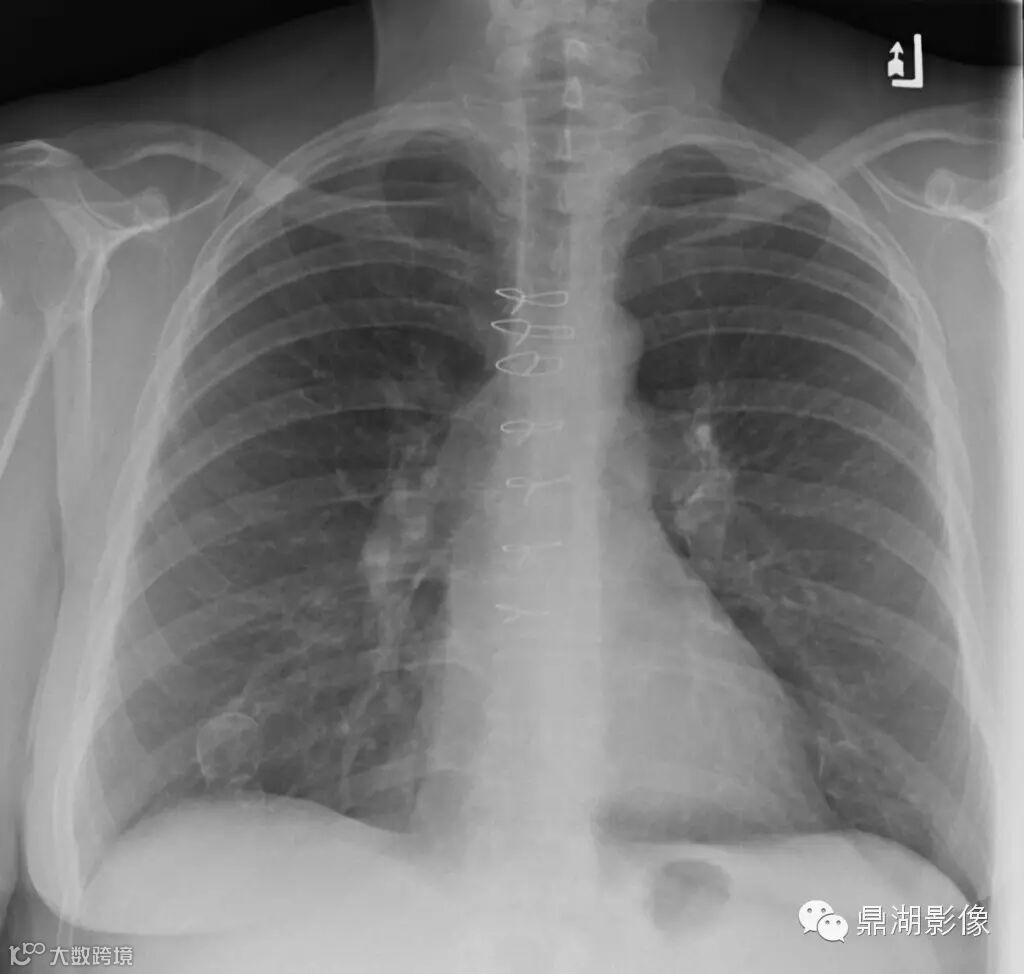

女,60,双侧乳房成形术数年,发现无痛性肿块数月。

双侧乳腺可见环状钙化

临床诊断:乳腺脂肪坏死

脂肪坏死临床及X线表现有如下特点:① 多有外伤、医源性损伤的病史,少数由导管扩张、炎症引起;② 临床上多为无痛性肿块和结节,质地偏硬,边缘欠清晰,少数有压痛;③伴有淋巴结肿大者,多为反应性增生,淋巴结光滑、质软、活动、无融合;④ 随访观察肿块无增大,反而逐渐缩小;⑤X线上脂性囊肿伴蛋壳样钙化以及皮下脂肪层内斑片状、星芒状、索条状及网状影为脂肪坏死的特征性表现。